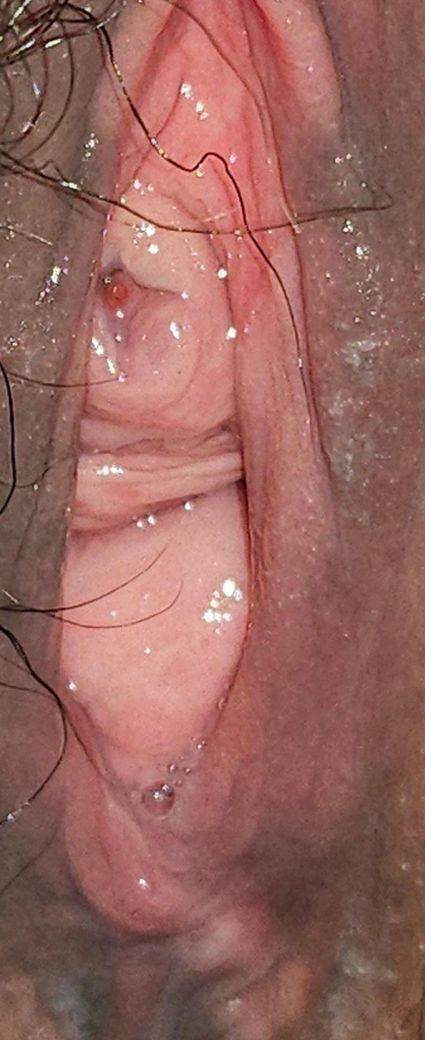

여성요도가 이상합니다 붓고 빨간증상 봐주세요

외음부에 포진이 나서 약바르면서

요도에 빨간뾰루지 같은걸 발견했어요 (한달전쯤)

-첫번째사진 : 처음발견당시 뾰루지처럼보임

-두번째사진 : 최근(외음부를 땡겨서 찍음)

-세번째사진 : 어제(외음부땡기지않고 찍음, 요도구윗쪽에 주름이 생김)

지난주에 사진찍어서 확인했을때는

뾰루지가 터진건지 퍼진건지

요도가 겉에도 안에도 전체적으로 붓고

요도안쪽이 빨개졌어요

• 1번 째 사진

• 2번 째 사진

• 3번 째 사진

1. 통증, 배뇨통, 발열, 탁한 소변, 혈뇨가 없고 한 달 이상 비교적 큰 변화 없이 유지되었다면 전형적인 세균성 요도염 가능성은 낮습니다. 사진상으로는 요도 입구 점막이 붉고 국소적으로 돌출된 형태가 보여 요도 카룬클(양성 점막 돌출)이나 출산 이후 점막 변화, 만성 자극에 의한 염증성 변화가 더 흔하게 고려됩니다. 요도암은 매우 드물고, 보통 지속적 출혈, 통증, 빠른 크기 증가가 동반되는 경우가 많습니다.

2. 정상 요도 입구는 개인차가 크고, 출산·호르몬 변화·복압 증가 이후에는 점막이 더 도톰하고 주름져 보일 수 있습니다. 사진에서는 요도 입구 및 주변 점막이 전체적으로 부어 있고 충혈된 모습은 맞지만, 종괴가 요도 깊숙이 침윤한 소견이나 명확한 궤양성 병변은 뚜렷하지 않습니다.